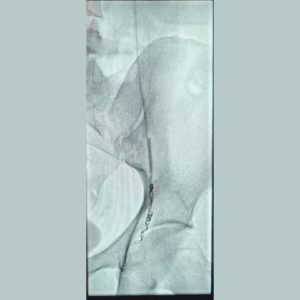

Our Solution: A tiny catheter is navigated into the affected veins. We then release tiny coils or a sclerosing agent to block these veins, redirecting blood flow to healthy pathways.

2. Uterine Artery Embolization (UAE)

For Post-Partum Haemorrhage (PPH): A life-saving procedure to stop uncontrolled bleeding after childbirth by pinpointing and blocking the bleeding vessels.